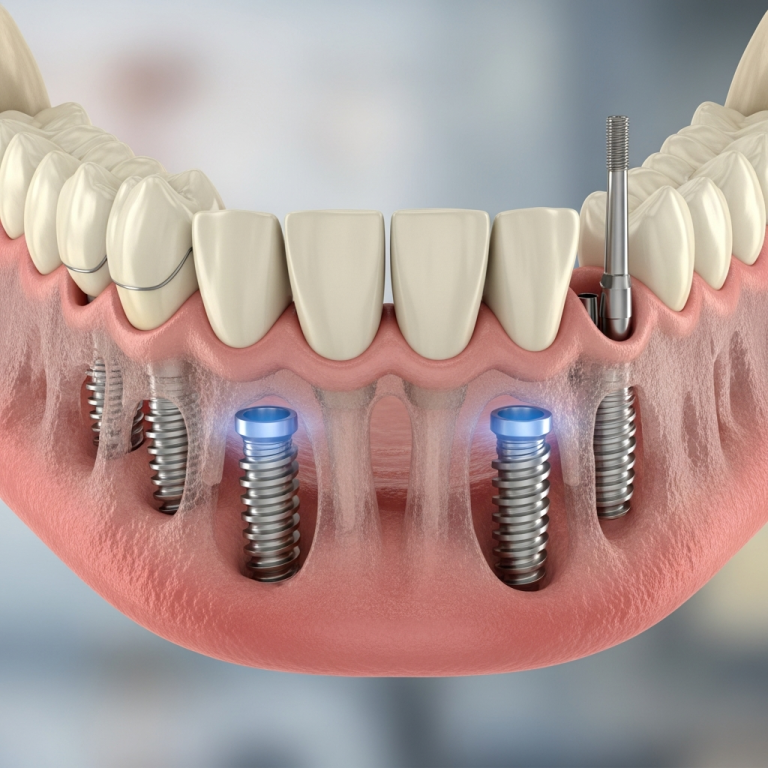

Implanturile bicorticale monobloc sunt sisteme integrate, unde piesa protetică (abutmentul) și corpul implantului formează o singură unitate structurală. Ele sunt proiectate strategic pentru a se ancora atât în corticala osoasă crestală, cât și în cea apicală (de exemplu, în sinus sau în regiunea nazală), oferind o stabilitate primară excepțională.

- Stabilitate primară maximă: Ancorarea dublă reduce micro-mișcările la sub 50 μm, prag critic pentru osteointegrare în condiții de încărcare imediată.

Tehnica de inserție și ancorare bicorticală

Succesul depinde de o planificare chirurgicală tridimensională riguroasă. Implantul este pozitionat astfel încât să atingă și să se sprijine pe cea de-a doua corticală, situată la baza regiunii implantare. Această tehnică necesită o evaluare precisă a volumului și densității osoase prin scanări CBCT și ghidaje chirurgicale.